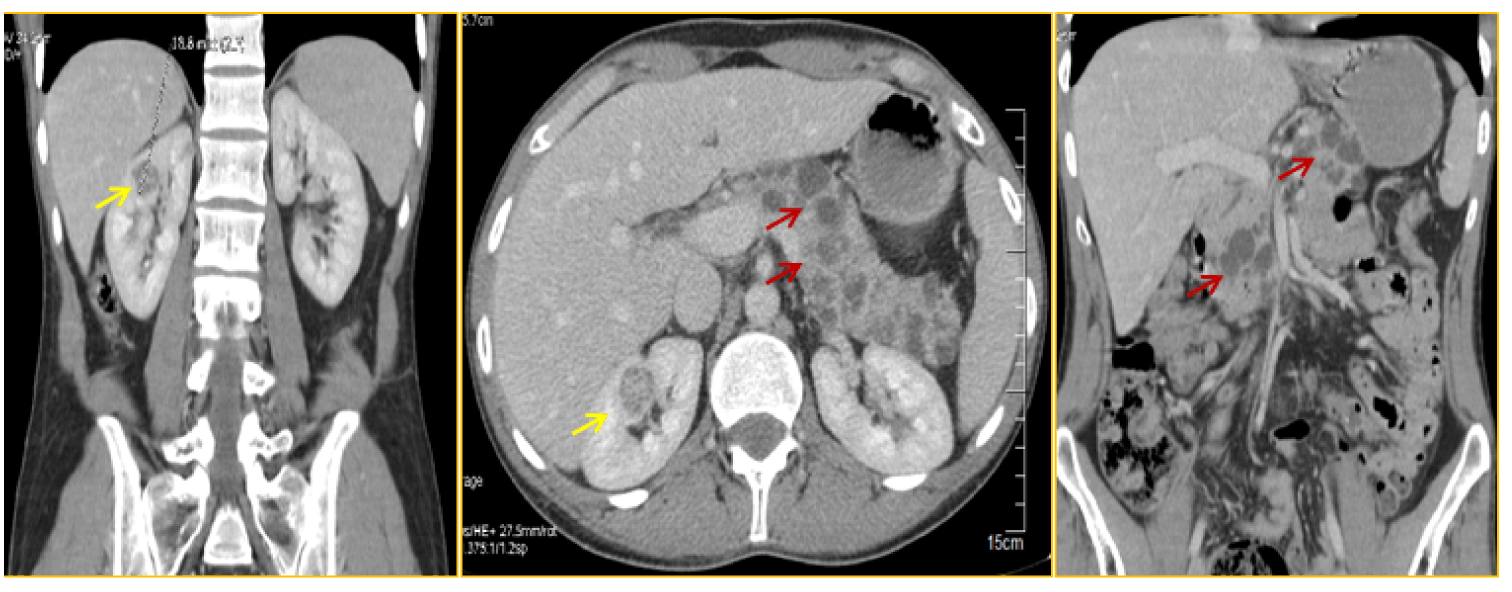

Figure 4: The abdominal computed tomography scan revealing two small renal masses (yellow arrow), less than 2 cm in size; with multiple pancreatic cysts (red arrow).

The patient underwent an MRI of the complete neuro-axis including brain and spinal cord showed a vermian hemangioblastoma associated with 2 small right cerebellar hemangioblastomas (Figure 3). The abdominal CT scan revealed 2 small renal masses, less than 2 cm in size; with multiple pancreatic cysts (Figure 4); without liver lesions, or adrenal masses. An ophthalmologic examination demonstrated none of the stigmatisms associated with VHL. Physical examination did not show any café au lait spots.